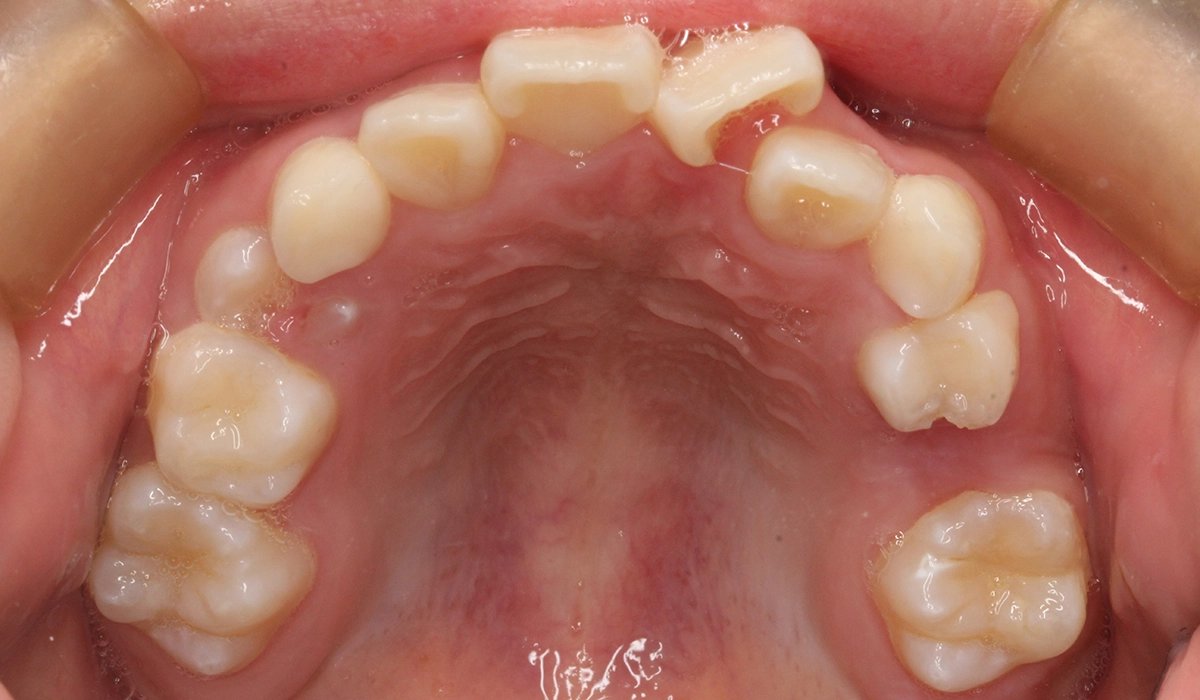

術前:上顎